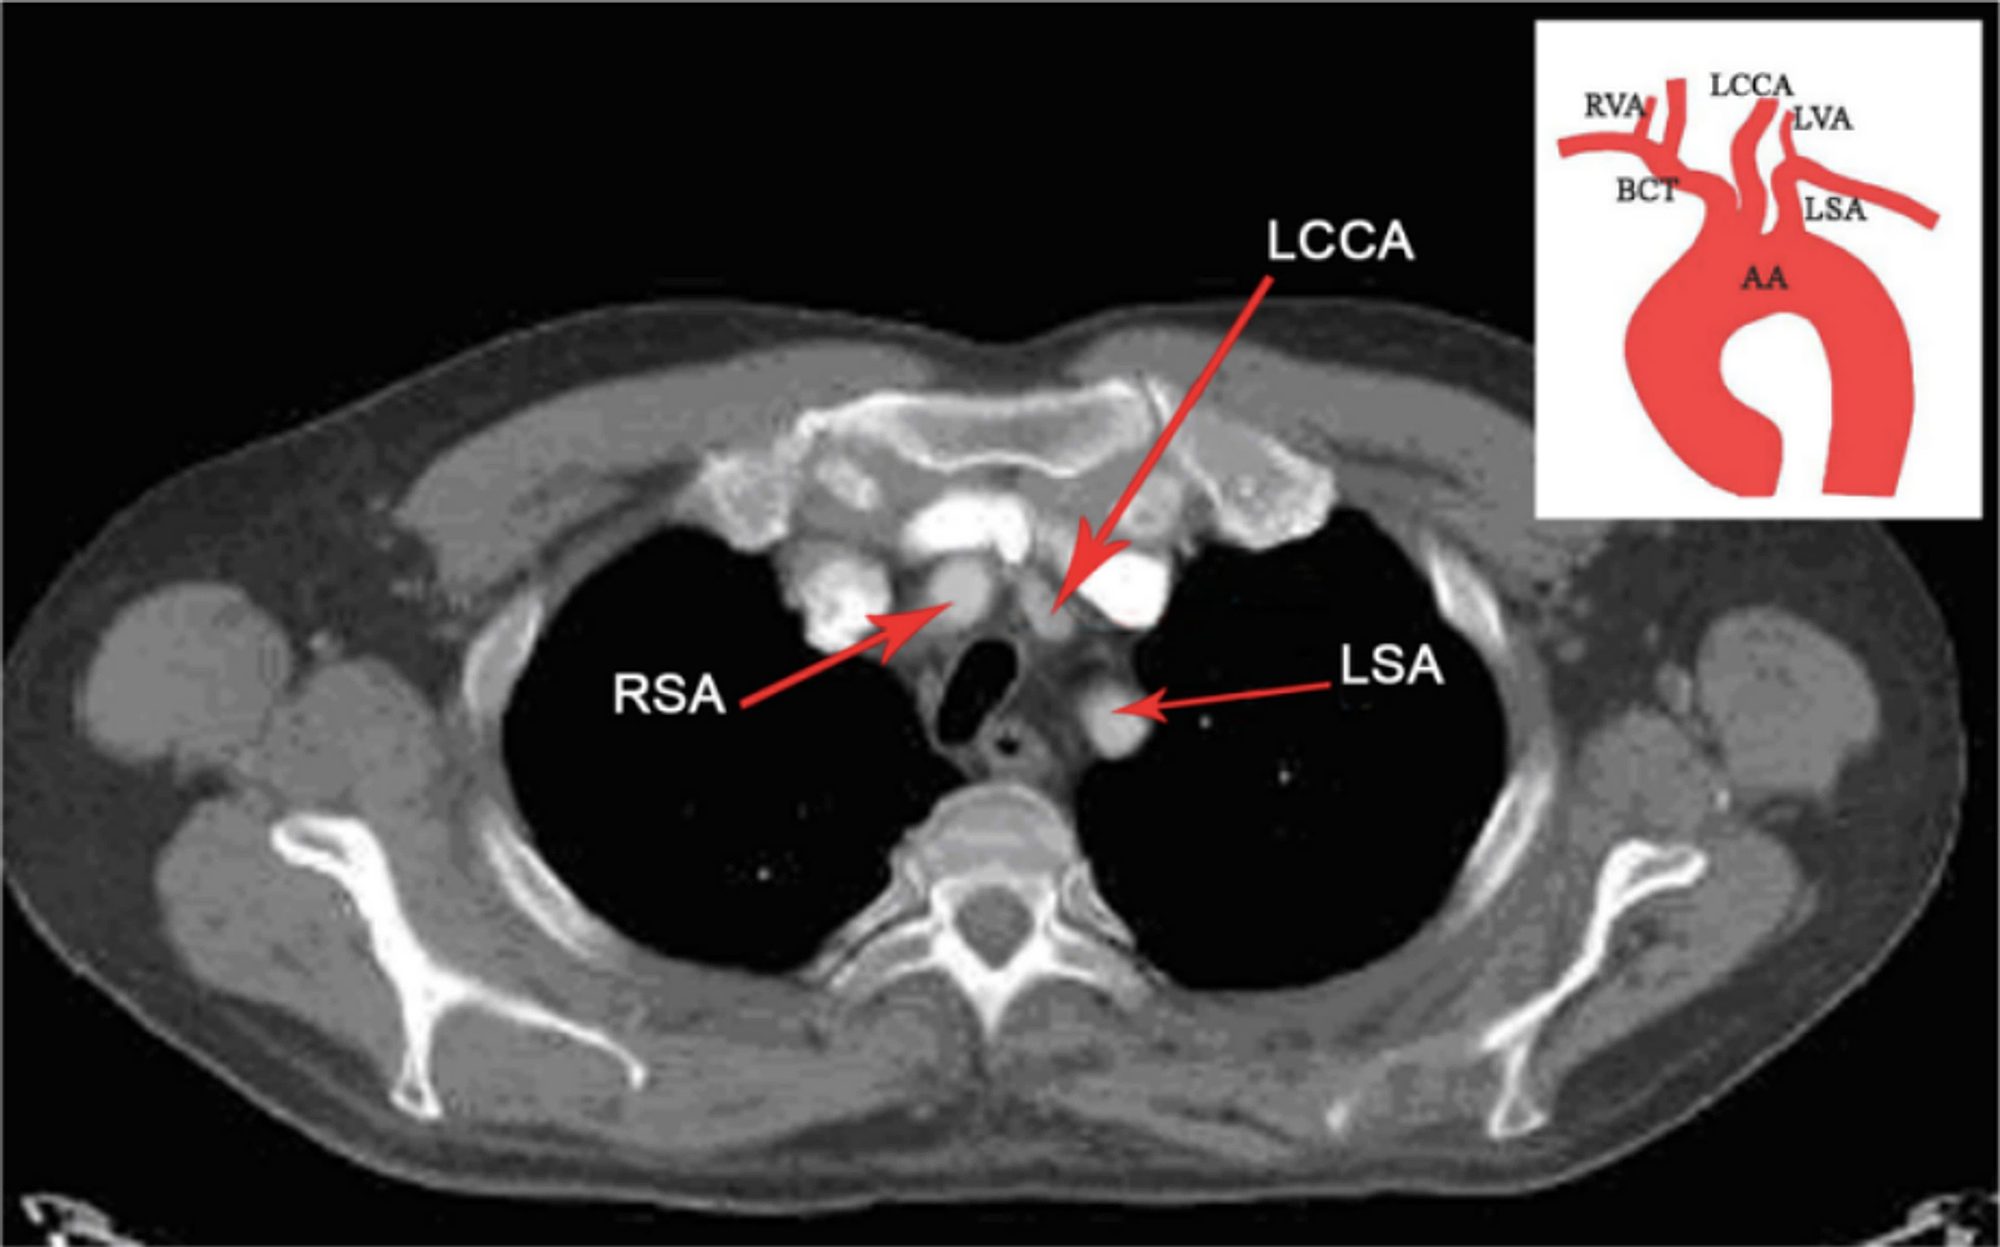

Thoracic aorta diagrams Radiology Case Subclavian

Thoracic aorta diagrams Radiology Case Subclavian Ct Anatomy Of Aorta The ascending aorta extends from the aortic valve to the origin of the innominate. Normal anatomy of the thoracic and abdominal aorta. The decision is based on the indication, clinical indications provided, and vascular access. Ct abdominal aorta can be performed with or without contrast. Ct and mri both offer potential for a thorough evaluation of the aorta and precise. Ct Anatomy Of Aorta.